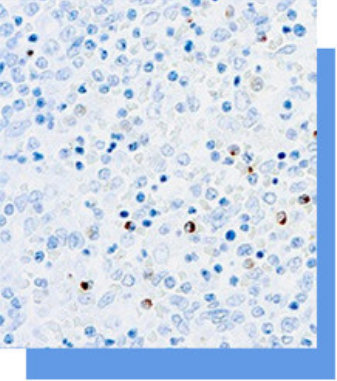

Perforin是细胞毒性T淋巴细胞中的孔道蛋白,

主要表达于CD3阴性而CD56阳性的NK细胞、CD3

阳性的大颗粒淋巴细胞和细胞毒性T淋巴细胞。其主

要应用于NK细胞淋巴瘤、NK细胞样T淋巴细胞淋巴

瘤的辅助诊断,有助于对NK细胞、细胞毒性T淋巴

细胞及肿瘤的研究。